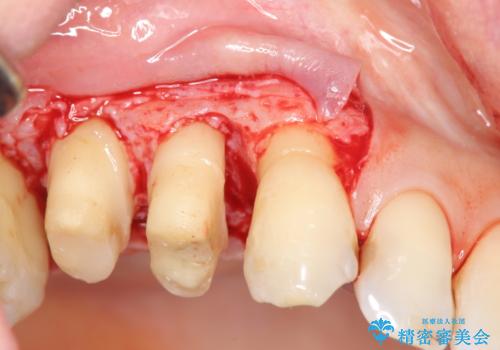

検査の結果、強い歯ぎしりによる歯の周囲の骨の吸収が認められたため歯槽骨の再生・歯周ポケットの除去・力に対抗する連結補綴・補綴前処置としての小矯正を計画します。

今回連結補綴を行うにあたり、歯周病の問題を解決するために再生療法・歯周ポケット除去手術を、またより歯の神経を保存し力に対抗できる環境を整えるために小矯正を行い精度の高いメタルボンドクラウンを製作することができました。